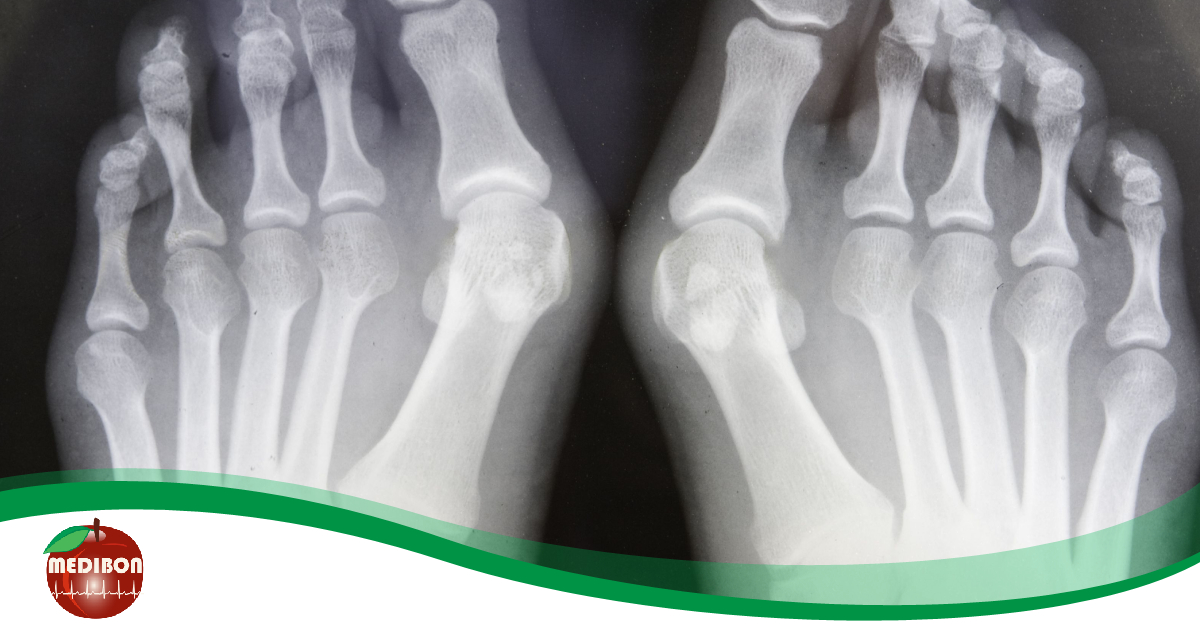

A hallux valgus, hétköznapi nevén bütyök, egyike a láb leggyakoribb deformitásainak. Akkor beszélhetünk bütyök kialakulásáról, ha a nagy lábujj alappercén csontkinövés keletkezik.

A nagyujj vagy más néven öregujj elhajlása okozza azt, hogy az alapperc az ellentétes oldalon kitüremkedik, és hosszabb távon csontkinövés jön létre.